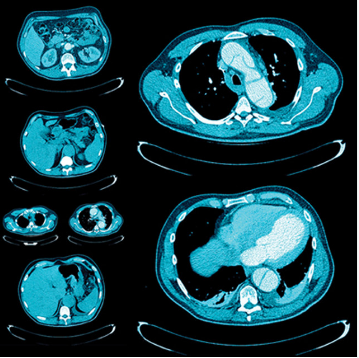

A comprehensive review of clinically relevant topics in thoracic and abdominopelvic imaging, this online video CME program lends special attention to imaging findings, reporting and management guidelines, and multimodality evaluation. Presenters — including UCSF and guest faculty — review indications commonly seen in general practice and highlight state-of-the-art imaging approaches.

Continuing medical education topics include pulmonary embolism, diffuse lung diseases, masses and malignancies of all major organs, emergent gastrointestinal conditions, multimodality evaluation of transplant donors and recipients, and more.

Additional sessions in UCSF Abdominal and Thoracic Imaging highlight procedures commonly performed by body radiologists, and the imaging evaluation of post-procedural complications.